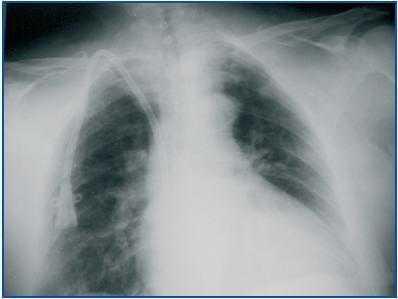

It is important that we do not confuse the approach to the innominate vein with the supraclavicular approach used to reach the subclavian vein. This is done by puncturing directly above the clavicle, but on the external side of the clavicular head of the sternocleidomastoid (figure 1) in the medial direction, requiring patency of the subclavian vein.10,11

Figure 1.